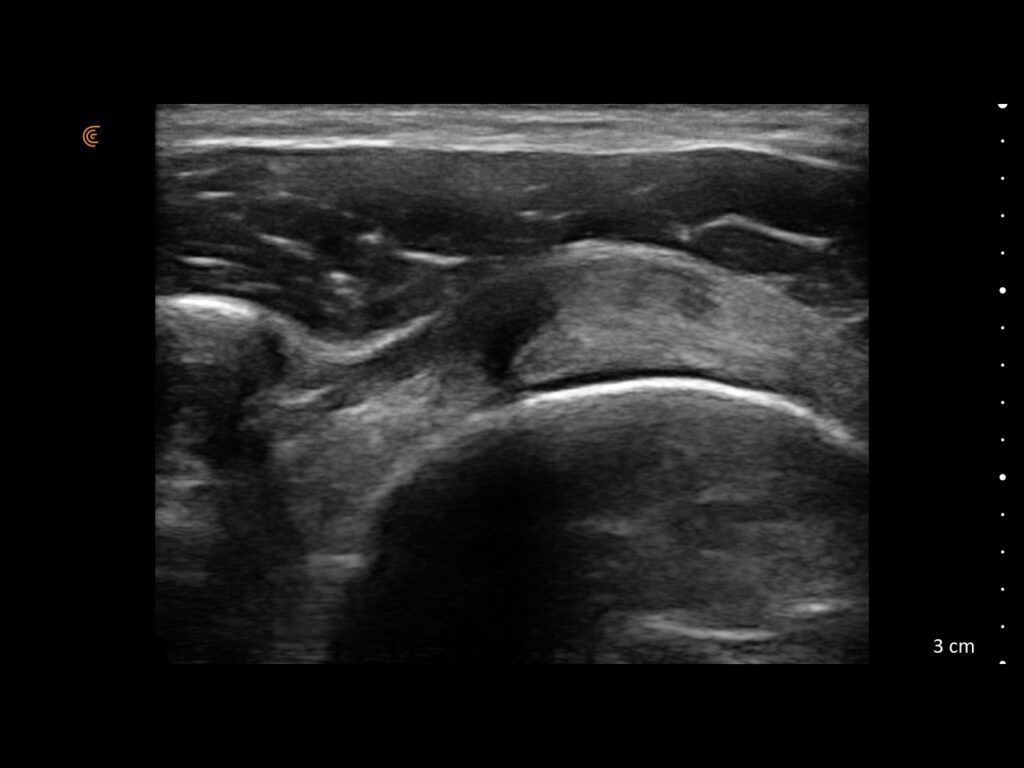

Visualize targets in real time to deliver PRP or cortisone—even in complex joints. Instantly diagnose sprains, tears, and effusions, and make confident decisions about surgical intervention

See Inflammation in Real Time.

Assess synovitis, enthesitis, and monitor treatment efficacy with high-resolution ultrasound, enabling precise, real-time joint and soft tissue evaluation, accurate needle guidance, and improved confidence in clinical decision-making.